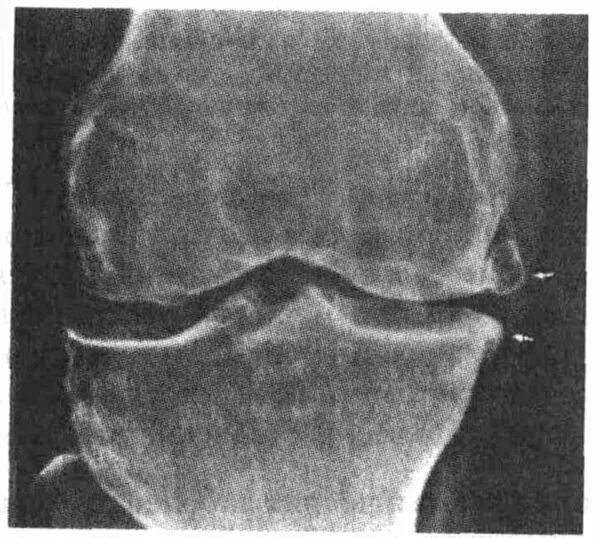

Остеосклероз суставов